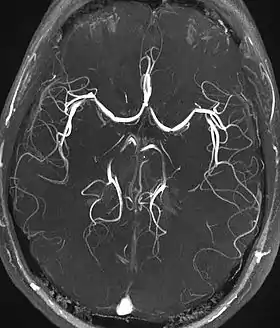

![]() Time-of-flight MRA showing the circle of Willis in the brain. Note the "venetian blinds" artifact visible as the multiple pseudo-stenosis on both the left and right middle cerebral artery | |